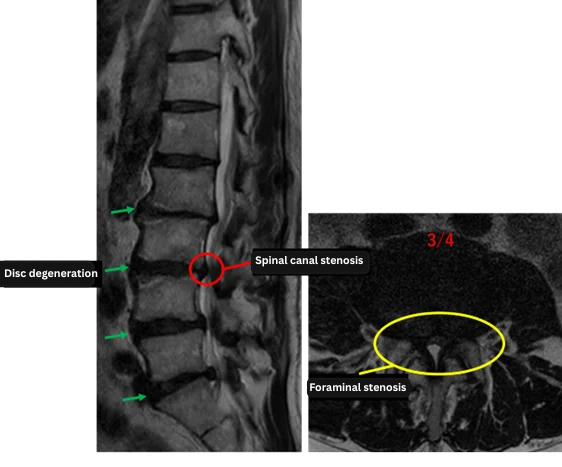

Imaging and findings

L1/2: —

L2/3: Disc degeneration, bulging, reduced disc height

L3/4: Disc degeneration, herniation, bilateral foraminal stenosis, ligamentum flavum hypertrophy, spinal canal stenosis

L4/5: Disc degeneration, bulging, bilateral foraminal stenosis

L5/S1: Disc degeneration, left-sided herniation, left foraminal stenosis

The above findings were also observed on the imaging.

These findings indicate that at L2/3, L3/4, L4/5, and L5/S1, there is a combination of disc degeneration, herniation, foraminal stenosis, ligamentum flavum hypertrophy, and lumbar spinal stenosis, which were considered highly likely to be the primary sources of the patient’s symptoms.